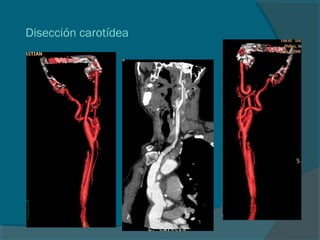

Disección carotídea